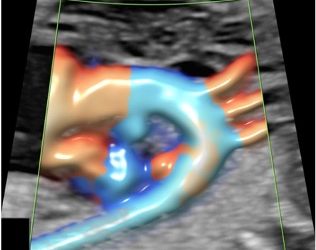

Cari soci, questo mese un nuovo video "How to do", sull'utilizzo del 3D nello studio dell'utero e dell'endometrio. Grazie a...